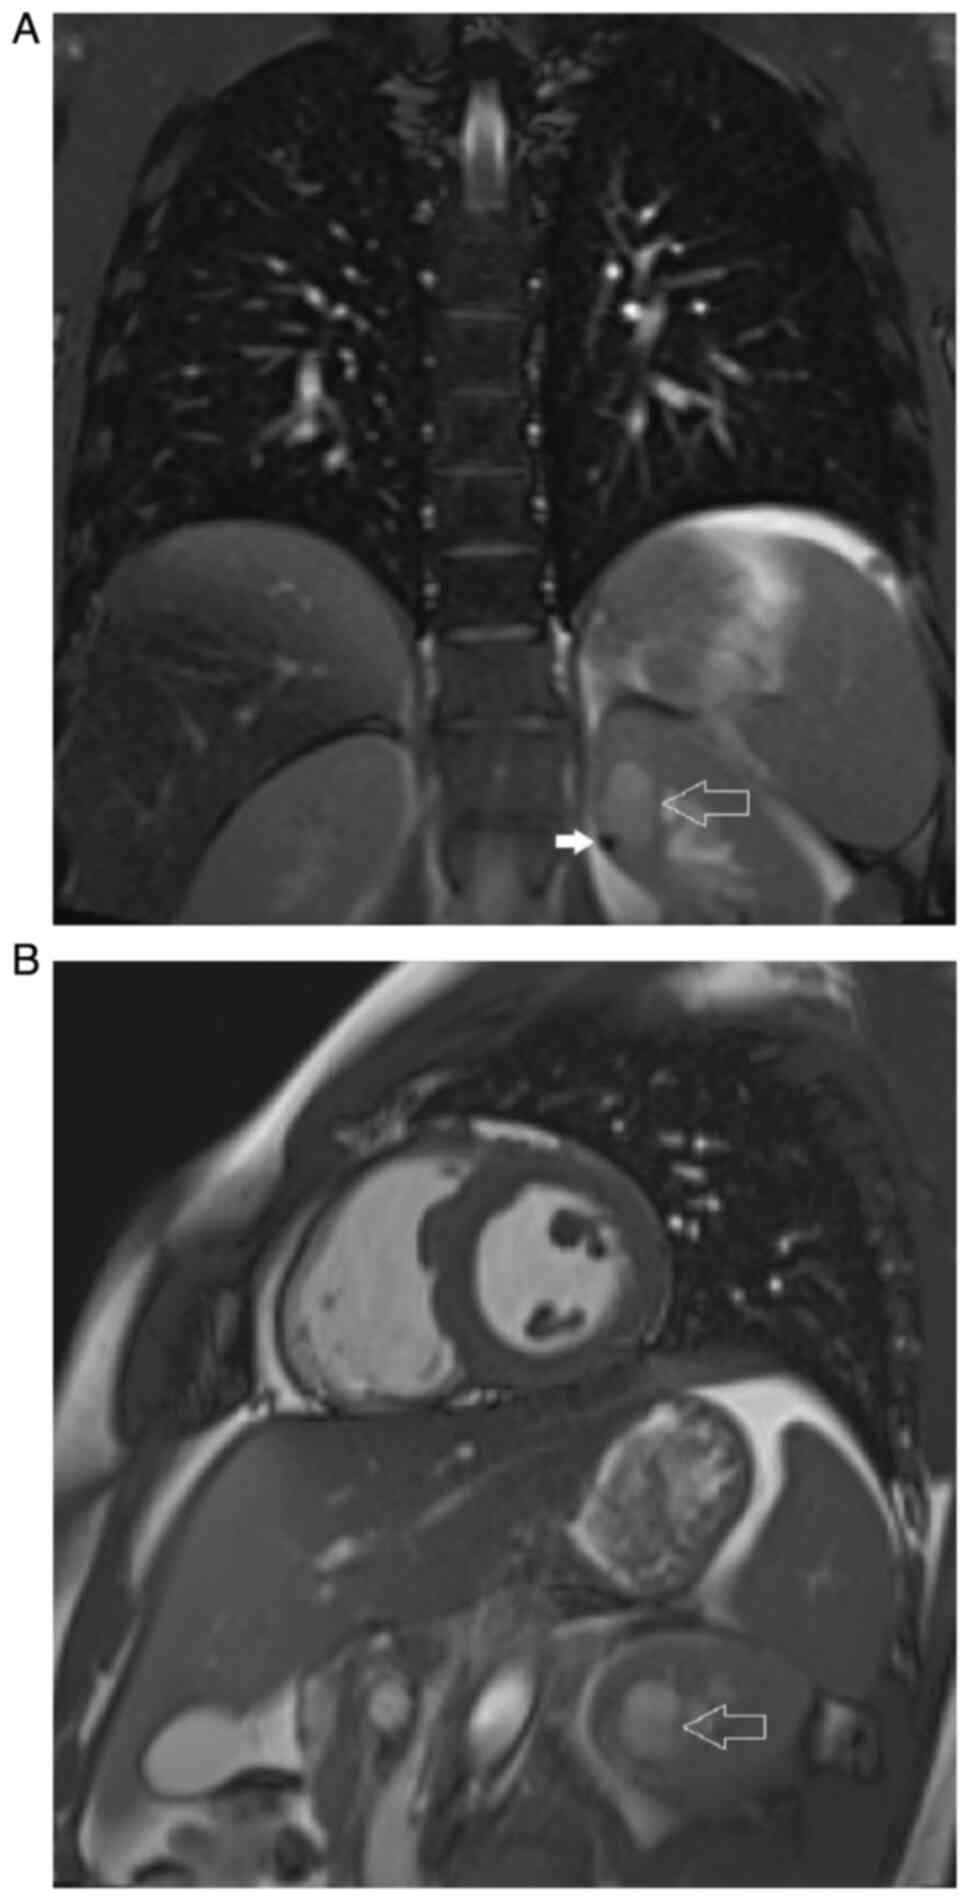

Mixed epithelial and stromal tumor of the kidney: A case report

Mixed epithelial and stromal tumor (MEST) is a rare neoplasm of the kidney, affecting mostly women at menopausal age. While few cases of malignant transformation have been described in the literature, MEST is usually considered a benign tumor with minimal risk of local recurrence or distance metastases. The current study presents a case of a 18‑year old male patient with a cystic tumor of the left kidney incidentally diagnosed on magnetic resonance imaging of the heart performed for other reasons. The patient underwent a partial nephrectomy, with perioperative course being uneventful. The pathology report revealed MEST of the kidney. No local recurrence nor disease progression have been observed in the patient during the one‑year follow‑up period. The present case report is evidence that may help in developing guidelines on the management of patients with benign renal masses.

Figure 2